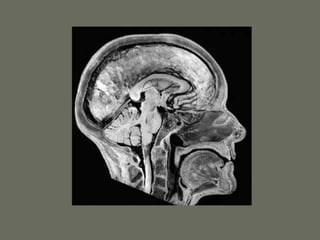

Parts of the Central Nervous

System

• 2 hemispheres

• Brainstem

• Cerebellum

• Spinal cord

Brainstem and Cranial Nerves

Brain stem

• Has 3 parts: midbrain, pons and medulla

• Transports all the information to and from

the brain

• Centers for breathing and blood pressure

• The origin or endpoint for cranial nerves

• Contains the center of consciousness

• Creates connections to the cerebellum